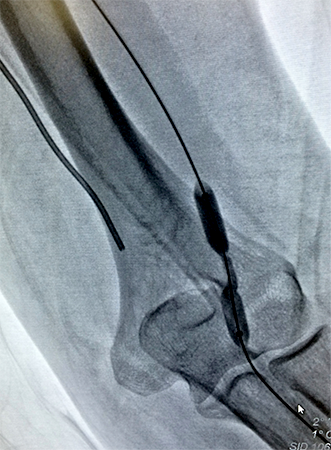

Angioplastias e Implantes de Stents

A falta de circulação para os diversos órgãos e membros pode ocorrer de maneira súbita ou gradual. As causas são as mais diversas, entre elas, trombose, aterosclerose, traumatismos, aneurismas, doenças inflamatórias, etc. Em alguns destes casos, a diminuição do fluxo sanguíneo determina um grave comprometimento à vitalidade do membro ou mesmo do órgão. A angioplastia consiste em reestabelecer a circulação para determinada parte do corpo através de pequenas punções, na maioria das vezes realizadas na região da virilha, evitando grandes incisões de pele. Os locais mais comuns de angioplastia periférica são: artérias dos membros inferiores, carótidas, artérias renais, entre outras. Após a melhora da circulação, o cirurgião vascular avalia a necessidade de utilizar um stent para melhorar o resultado e a durabilidade da angioplastia. Existem diversos tipos de balões de angioplastia e stents disponíveis no mercado, cabendo ao especialista identificar qual o melhor material indicado para cada situação.